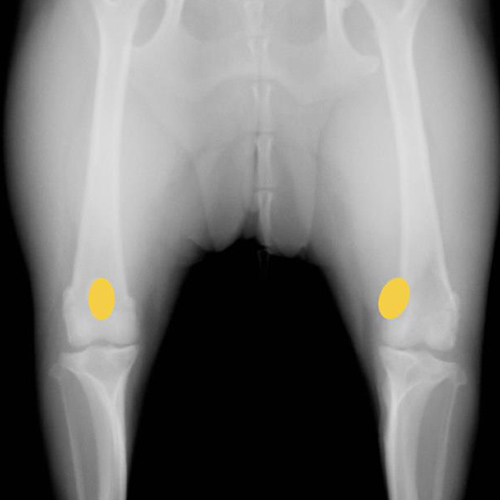

膝蓋骨内方脱臼のX線写真です。(2枚とも同じ症例)

黄色い丸で示された膝蓋骨が反対側と比較して内側にずれているのが確認できます。この脱臼により、膝本来の正常な曲げ伸ばしが障害され、時間をかけて様々な問題を併発させます。